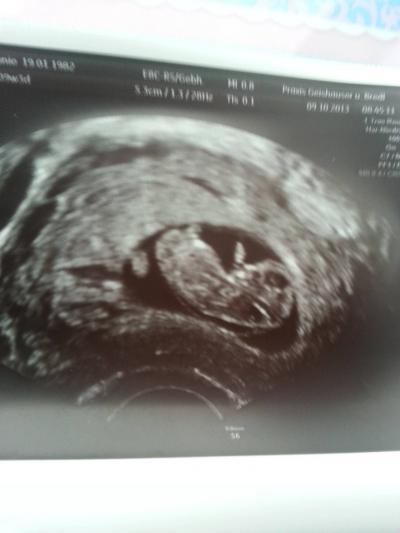

auf dem ultraschallbild von heute... ist ein dünner strich unterhalb vom rücken.. der sollte bis in 2,3 wochen dann zurückgebildet sein,angeblich jetzt noch normal.... wer kennt das oder hat des auch?

Bild zu bissl sorge - Forum für Mai - Mamis

Die Ärztin sagte, das wäre jetzt normal. Muss aber in 2 bis 3 wochen weg sein.Da sonst was nicht sstimmt. Ich hab schon 2 kiddis und da war dieser szreifen net hm....ich bin 9plus3ssw

Könnte es vielleicht sein das dass die nackenfalte ist ? Ich hab zwar gelesen das man sie ert ab der 11 ssw messen sollte aber evt. Kann man sie ja schon vorher sehen ?!? Ich bin mir wirklich nicht sicher, aber das könnte ich mir gut vorstellen. Aber es wird bestimmt alles gut werden, immer positiv denken :)

ja is nackenfalte. jetz hab ichs wieder

Achso und ich hab mor ebend mein us bild nochmal angeschaut bin heute 9+3 ssw und wenn man gaanz genau hinschaut sieht man ebendfalls diese Linie , unsere Bildchen sind ziemlich ähnlich ;)